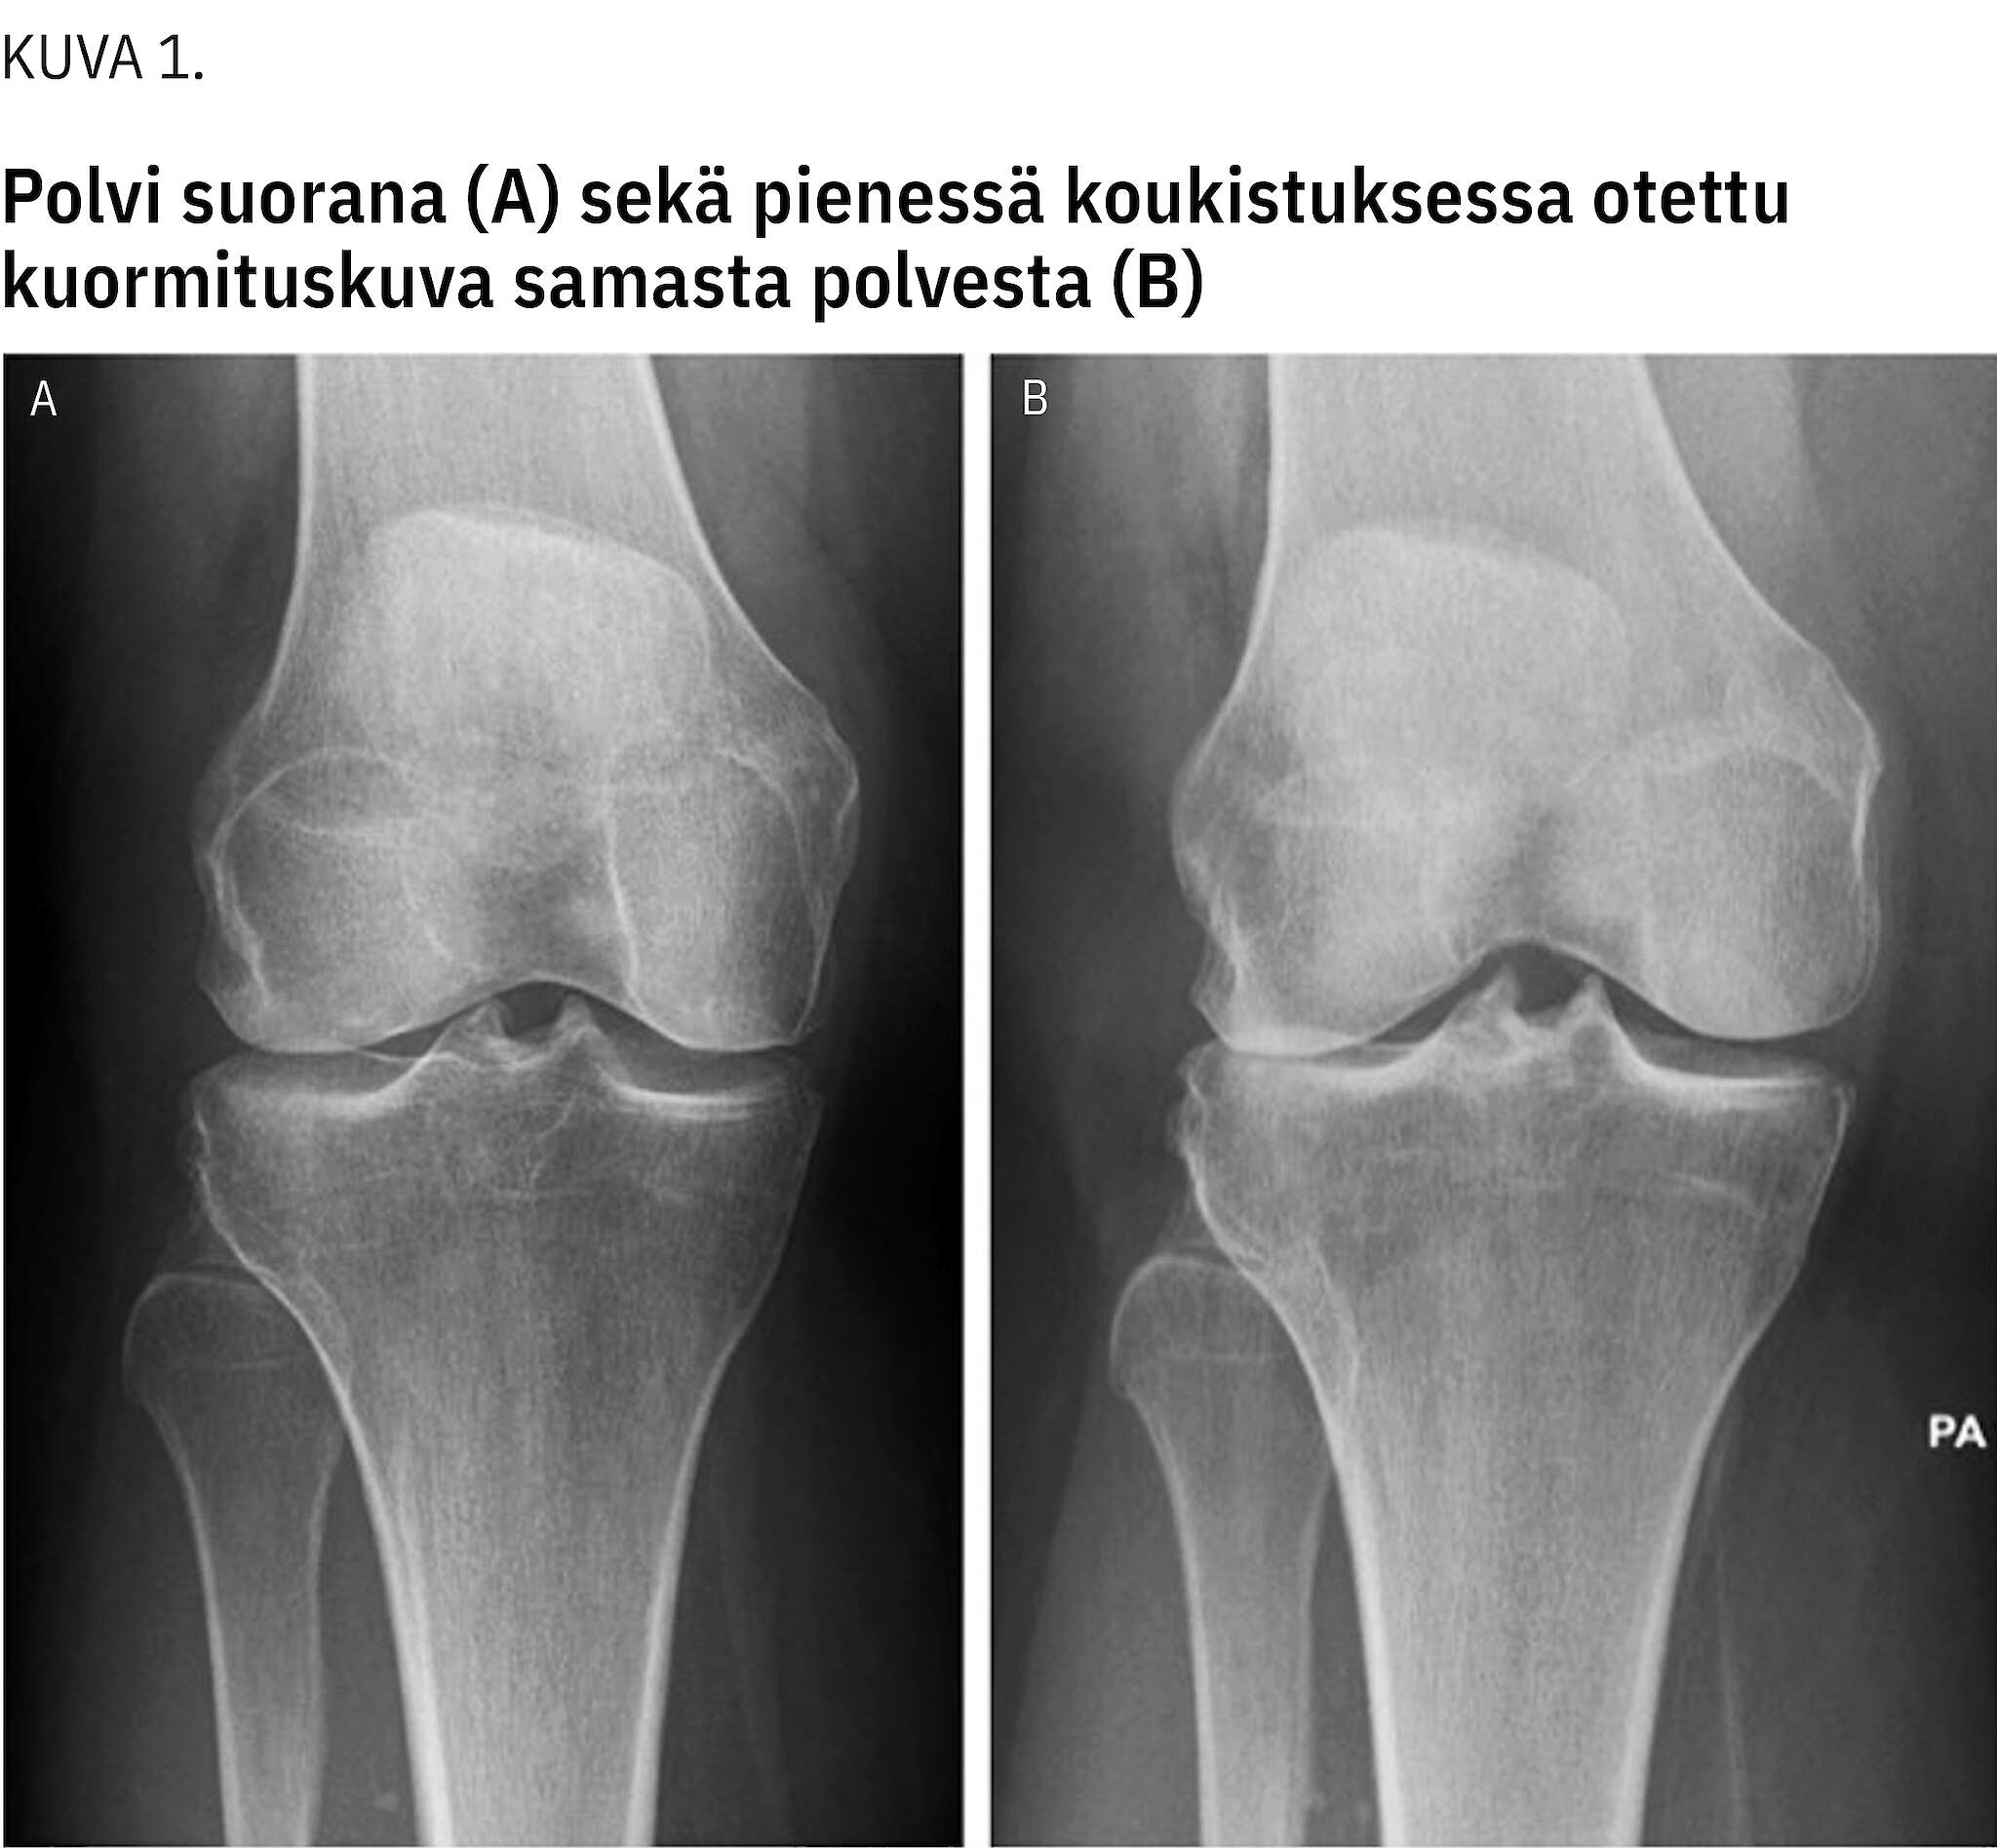

Degeneratiivisissa polvikivuissa röntgenkuvat pyritään aina ottamaan seisten, polvi 10–20 asteen koukistuksessa. Kuormittamatta tai polvi suorana otettu kuva voi merkittävästi aliarvioida nivelrikon astetta (kuva 1).

Tyypillisimmät polven nivelrikkoon liittyvät radiologiset löydökset ovat nivelraon kaventuminen, osteofyytit ja skleroosi. Pitkälle edenneessä kulumassa näkyy luiden päiden muotoutuminen.